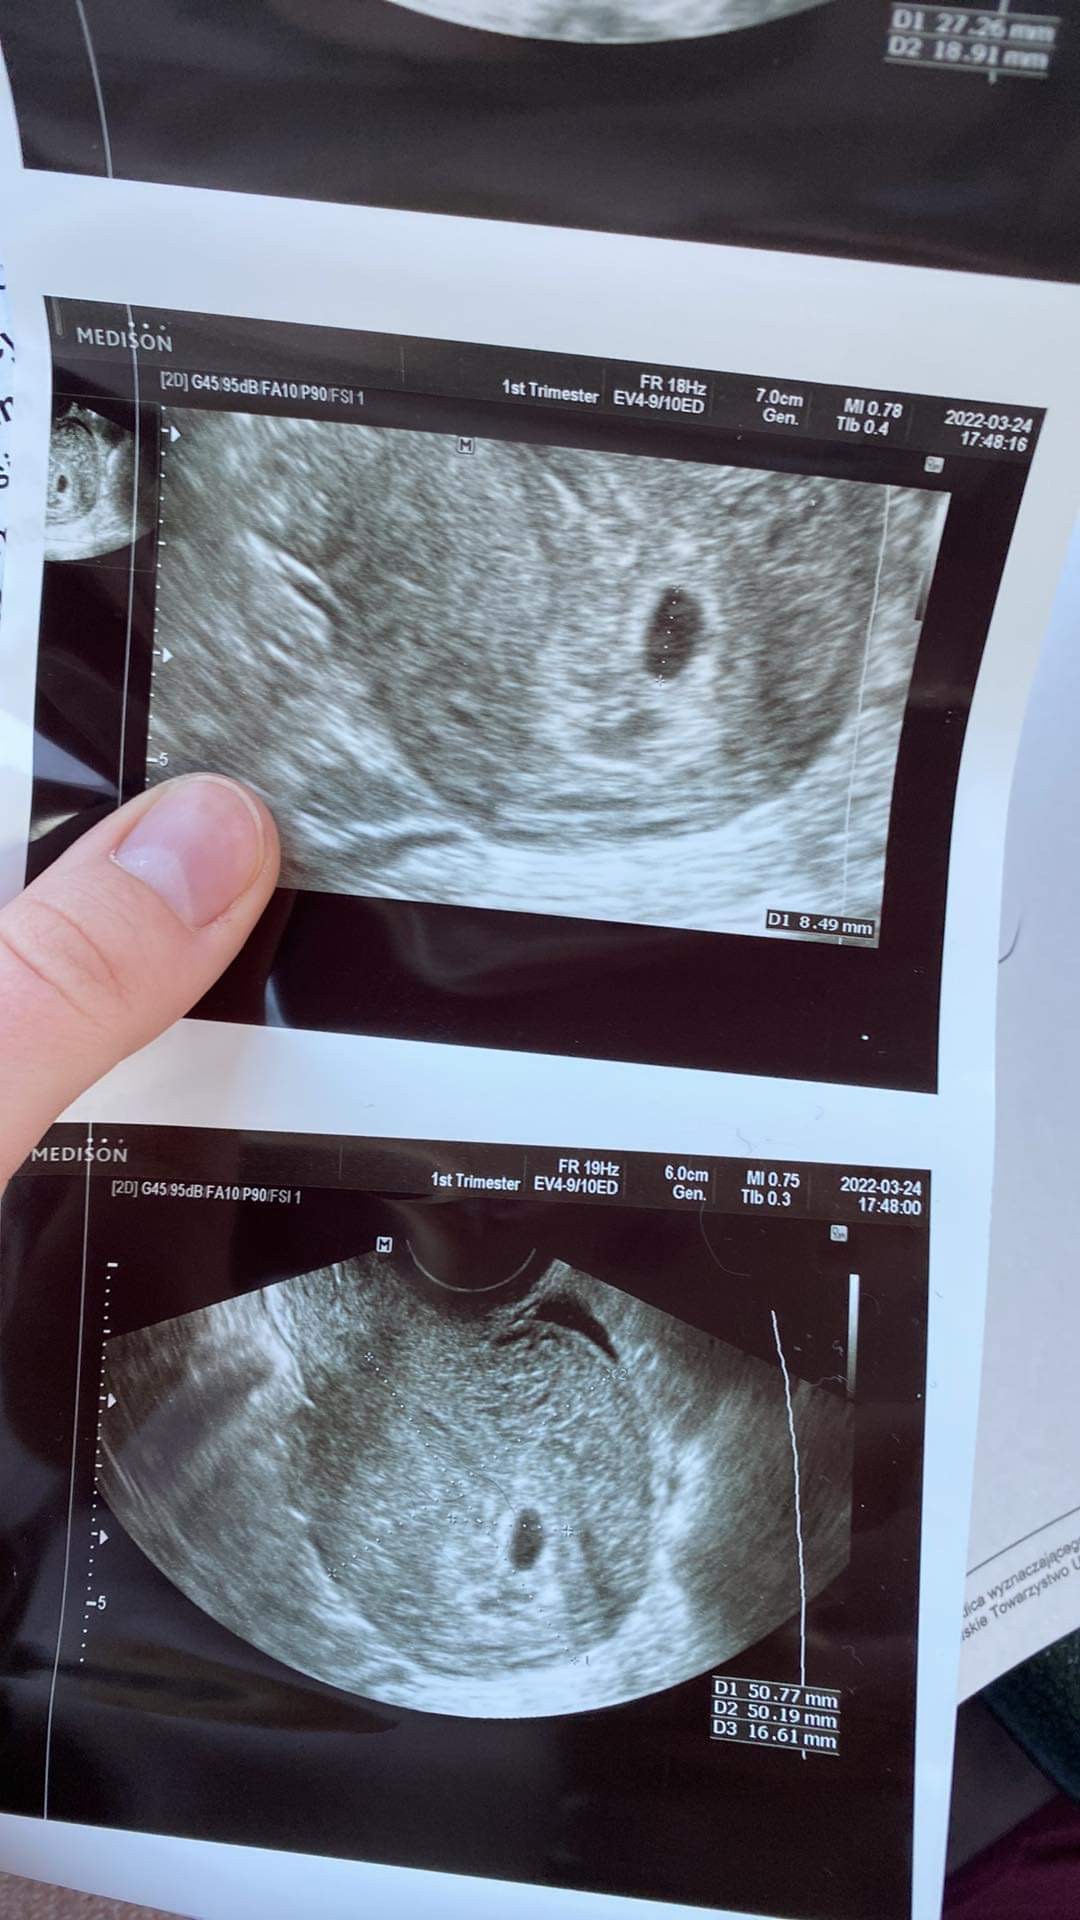

U nas po wczorajszej wizycie wszystko dobrze… pozdrawiamy :)

Zobacz załącznik 1382092

Właśnie wróciłam od lekarza :D 5+6 wg OM , jest piękny pęcherzyk ciążowy - za 10 dni mam wrócić i podobno już zobaczymy serduszko 🥰🥰 ale się cieszę

Załączniki

• E0891999-8565-43D8-8EF0-BE0673108084.jpeg

E0891999-8565-43D8-8EF0-BE0673108084.jpeg

228,9 KB · Wyświetleń: 87

@agutkowa19 piękny pęcherzyk. Za 10 już będzie zasuwać.

Jestem mamą dwóch synków 3 lata i 11 msc, teraz termin z usg pokazuje 14.11, a z OM 06.11. Z racji tego, że karmię laktacja mogła się przesunąć. Na ostatniej wizycie byłam 21.03 i było już serduszko 🧡. Test robilam 02.03 i to był cień cienia, gdyby nie objawy, które nie dawały mi spokoju nie pojechałabym na betę. Wtedy była malutka 11,47. Na Usg 05.03 u lekarza nie było nic widać poza śluzówką typową dla ciąży. Kolejne usg 14.03 widoczny malutki pęcherzyk, a teraz w pon juz serduszko.